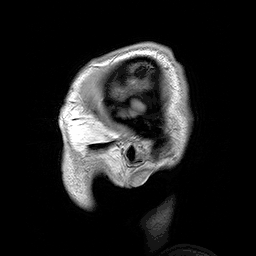

| Para-sagittal MRI of the head in a patient with benign familial macrocephaly | |